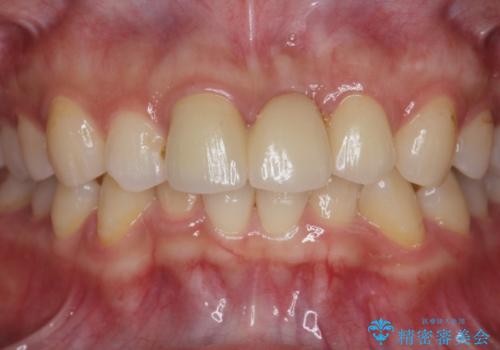

長期的な予後を見通すことが難しかったので、亀裂のある前歯の抜去を行いブリッジで審美性・機能性の回復を行いました。

- 36.3万円(仮歯・ジルコニアクラウン×3)費用は治療当時の料金となります

歯ぐきの腫れや排膿を繰り返す場合、亀裂や破折、根管の感染、歯周病等の考えうる原因を見極め、適切な処置を行うことが大切です。